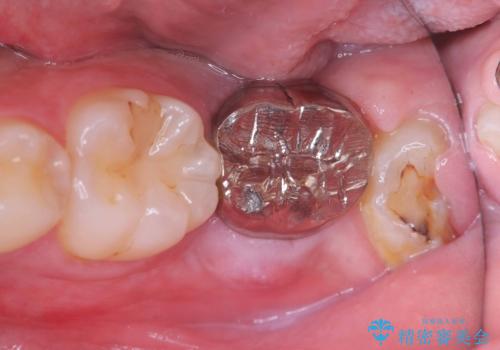

- 「歯茎の腫れ」を主訴に来院された患者様です。検査の結果、エンドペリオ病変と診断いたしました。

治療方針としては、保存的治療と抜歯後のインプラント治療の2つの選択肢をご提案させていただきました。

患者様ご自身が抜歯後のインプラント治療をご希望されたため、インプラントによる治療を行いました。